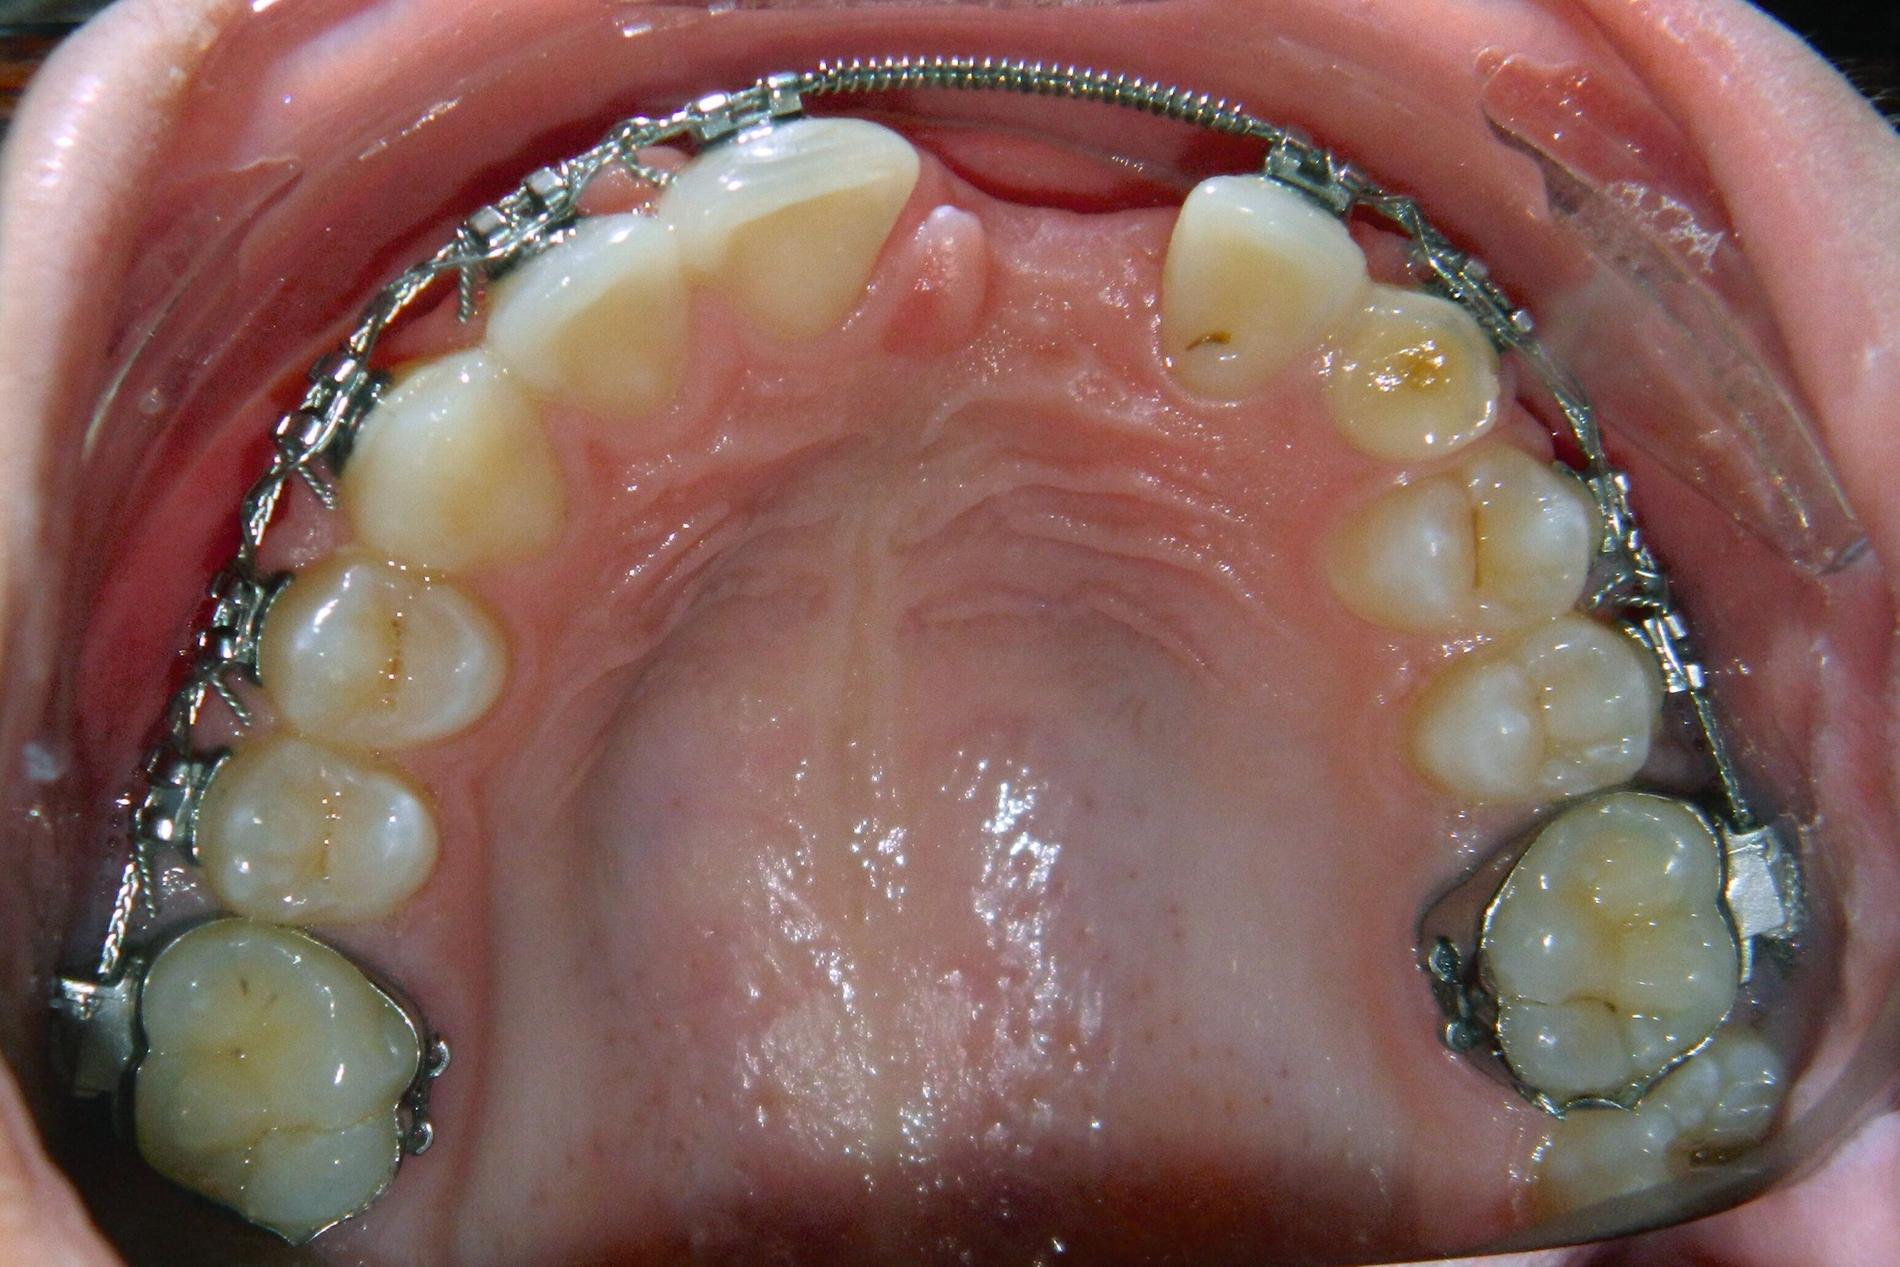

Im Februar 2019 wurde die kieferorthopädische Klinik von der Erstautorin übernommen. Bei der Auswertung der vorgefundenen Daten der Patientin wurde festgestellt, dass der linke obere zentrale Schneidezahn vor sechs Monaten extrahiert worden war. Die festsitzende Apparatur war im Oberkiefer bereits eingegliedert. Die Druckfeder zwischen Zahn 11 und 22 diente zur Lückenöffnung für den späteren prothetischen Ersatz des Zahnes 21. Auch auf den persistierenden linken Milcheckzahn war ein Bracket geklebt. Die Okklusion im Bereich der ersten Molaren war rechts und links neutral (Abbildung 2).

Das Bracket auf dem linken Milcheckzahn wurde entfernt, um einer weiteren Wurzelresorption und einem früheren Milchzahnverlust vorzubeugen, da dieser Zahn als Platzhalter belassen werden sollte. Des Weiteren war es von entscheidender Bedeutung, den Prozess der Atrophie des Alveolarkamms zu verhindern, um die spätere Insertion eines Implantats regio 23 zu ermöglichen.